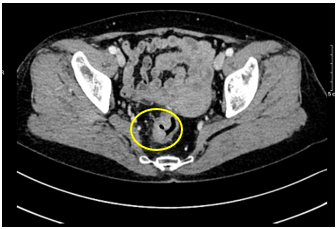

- CT scanner ổ bụng : chưa phát hiện hình ảnh tái phát tại miệng nối

Hình 4: Hình ảnh miệng nối đại–trực tràngqua CLVT, miệng nối thông tốt, không ghi nhận rò rỉ/ bục miệng nối, không có tụ dịch, không thấy khối bất thường choán chỗ.